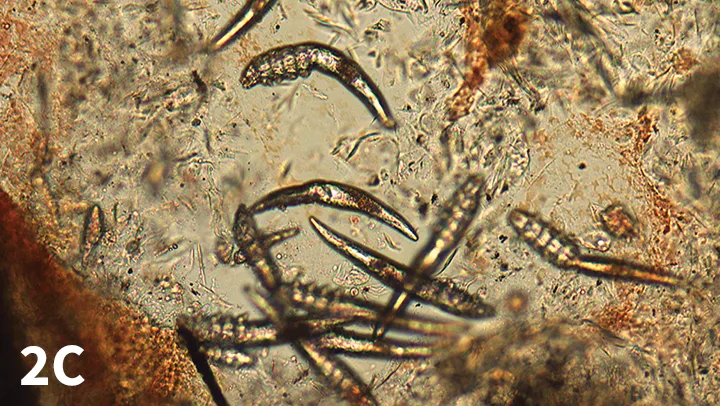

When examining, confirm that small drops of reddish material are present; this is blood (Figure 2C) and confirms the scraping was sufficiently deep.

FIGURE 2C

Multiple Demodex spp mites along with reddish material, confirming a deep scraping.